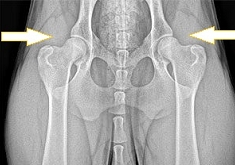

犬の股関節 (レントゲン画像)

正常な股関節

左右対称で

寛骨臼内に大腿骨頭が正しく収まっている

股関節形成不全症

寛骨臼が不完全で

大腿骨頭が収まっていない

片方は寛骨臼が無く

大腿骨頭が飛びだしている